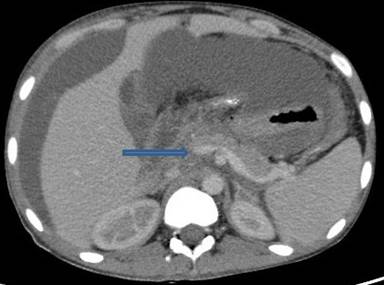

A 30-year-old man presented to our outpatient clinic with history of abdominal distention without pedal edema for the past 3 months. He also had deep boring epigastric pain and vomiting for 2 months. He had noticed low grade fever and anorexia for last 15 days. He had been consuming alcohol (100 g/day) for last 5 years (last drink 3 months back). Examination revealed pallor, facial puffiness, tachycardia, ascites and bilateral pleural effusion. His neck veins were engorged and hepatojugular reflex was absent. On investigation ascitic fluid was hemorrhagic with proteins 5.5 g/dL (reference range: 0-0.5 g/dL); white blood cells were 215 mm-3 (reference range: 0-5 mm-3; polymorphs 35% and lymphocytes 65% in a background of red blood cells). Ascitic fluid adenosine deaminase was 20 IU/mL (reference range: 0-35 IU/mL) and ascetic fluid amylase 58,840 IU/L (reference range: 0-100 IU/L). Pleural fluid was also hemorrhagic with protein 5.5 g/dL (reference range: 0-0.5 g/dL), white blood cells 80 mm-3 (polymorphs 50%, lymphocytes 50%) and adenosine deaminase was 35 IU /mL. 2D echo was normal. Serum amylase was 700 IU/L (reference range: 0-150 IU/L), serum lipase was 3,526 IU/L (reference range: 0-150 IU/L), and pleural fluid amylase was 5,748 IU/L (reference range: 0-50 IU/L). CT scan showed thromboses of bilateral subclavian and internal jugular vein, superior vena cava, infra renal inferior vena cava, a segment of suprarenal and infrahepatic inferior vena cava and right common iliac vein and patent splanchnic veins (Figures 1-5). Color Doppler abdomen showed normal portal vein of 10 mm diameter with hepatopetal flow, normal retrohepatic inferior vena cava with hepatopetal flow, while rest of inferior vena cava was thrombosed; all three hepatic veins well visualized with normal flow (Figure 6). MRCP revealed acute inflammation with underlying chronic pancreatitis with stricture at junction of head and body with intraductal calculi with leak at head and body junction and multiple loculated intra abdominal collections. The prothrombotic work up, including factor V Leiden, JAK 2 mutation, homocysteine, antiphospholipid antibody, protein C and S, and antithrombin III, was negative. Thus, a diagnosis of chronic pancreatitis with pancreatic ascites and pleural effusion with multiple extrasplanchnic thromboses due to pancreatitis was made. Patient was managed conservatively with intravenous heparin, initially continuous infusion of 1,000 units/hour and later on oral anticoagulants. ERCP with pancreatic sphincterotomy was done and a 5Fr x 10 cm stent was placed. Patient symptomatically improved with complete disappearance of ascites. His repeat color Doppler showed partial recanalization of superior vena cava, internal jugular vein and subclavian veins (Figure 7).

Figure 1. CECT axial view shows thrombosis in right common iliac vein (arrow), there is presence of gross ascites. |